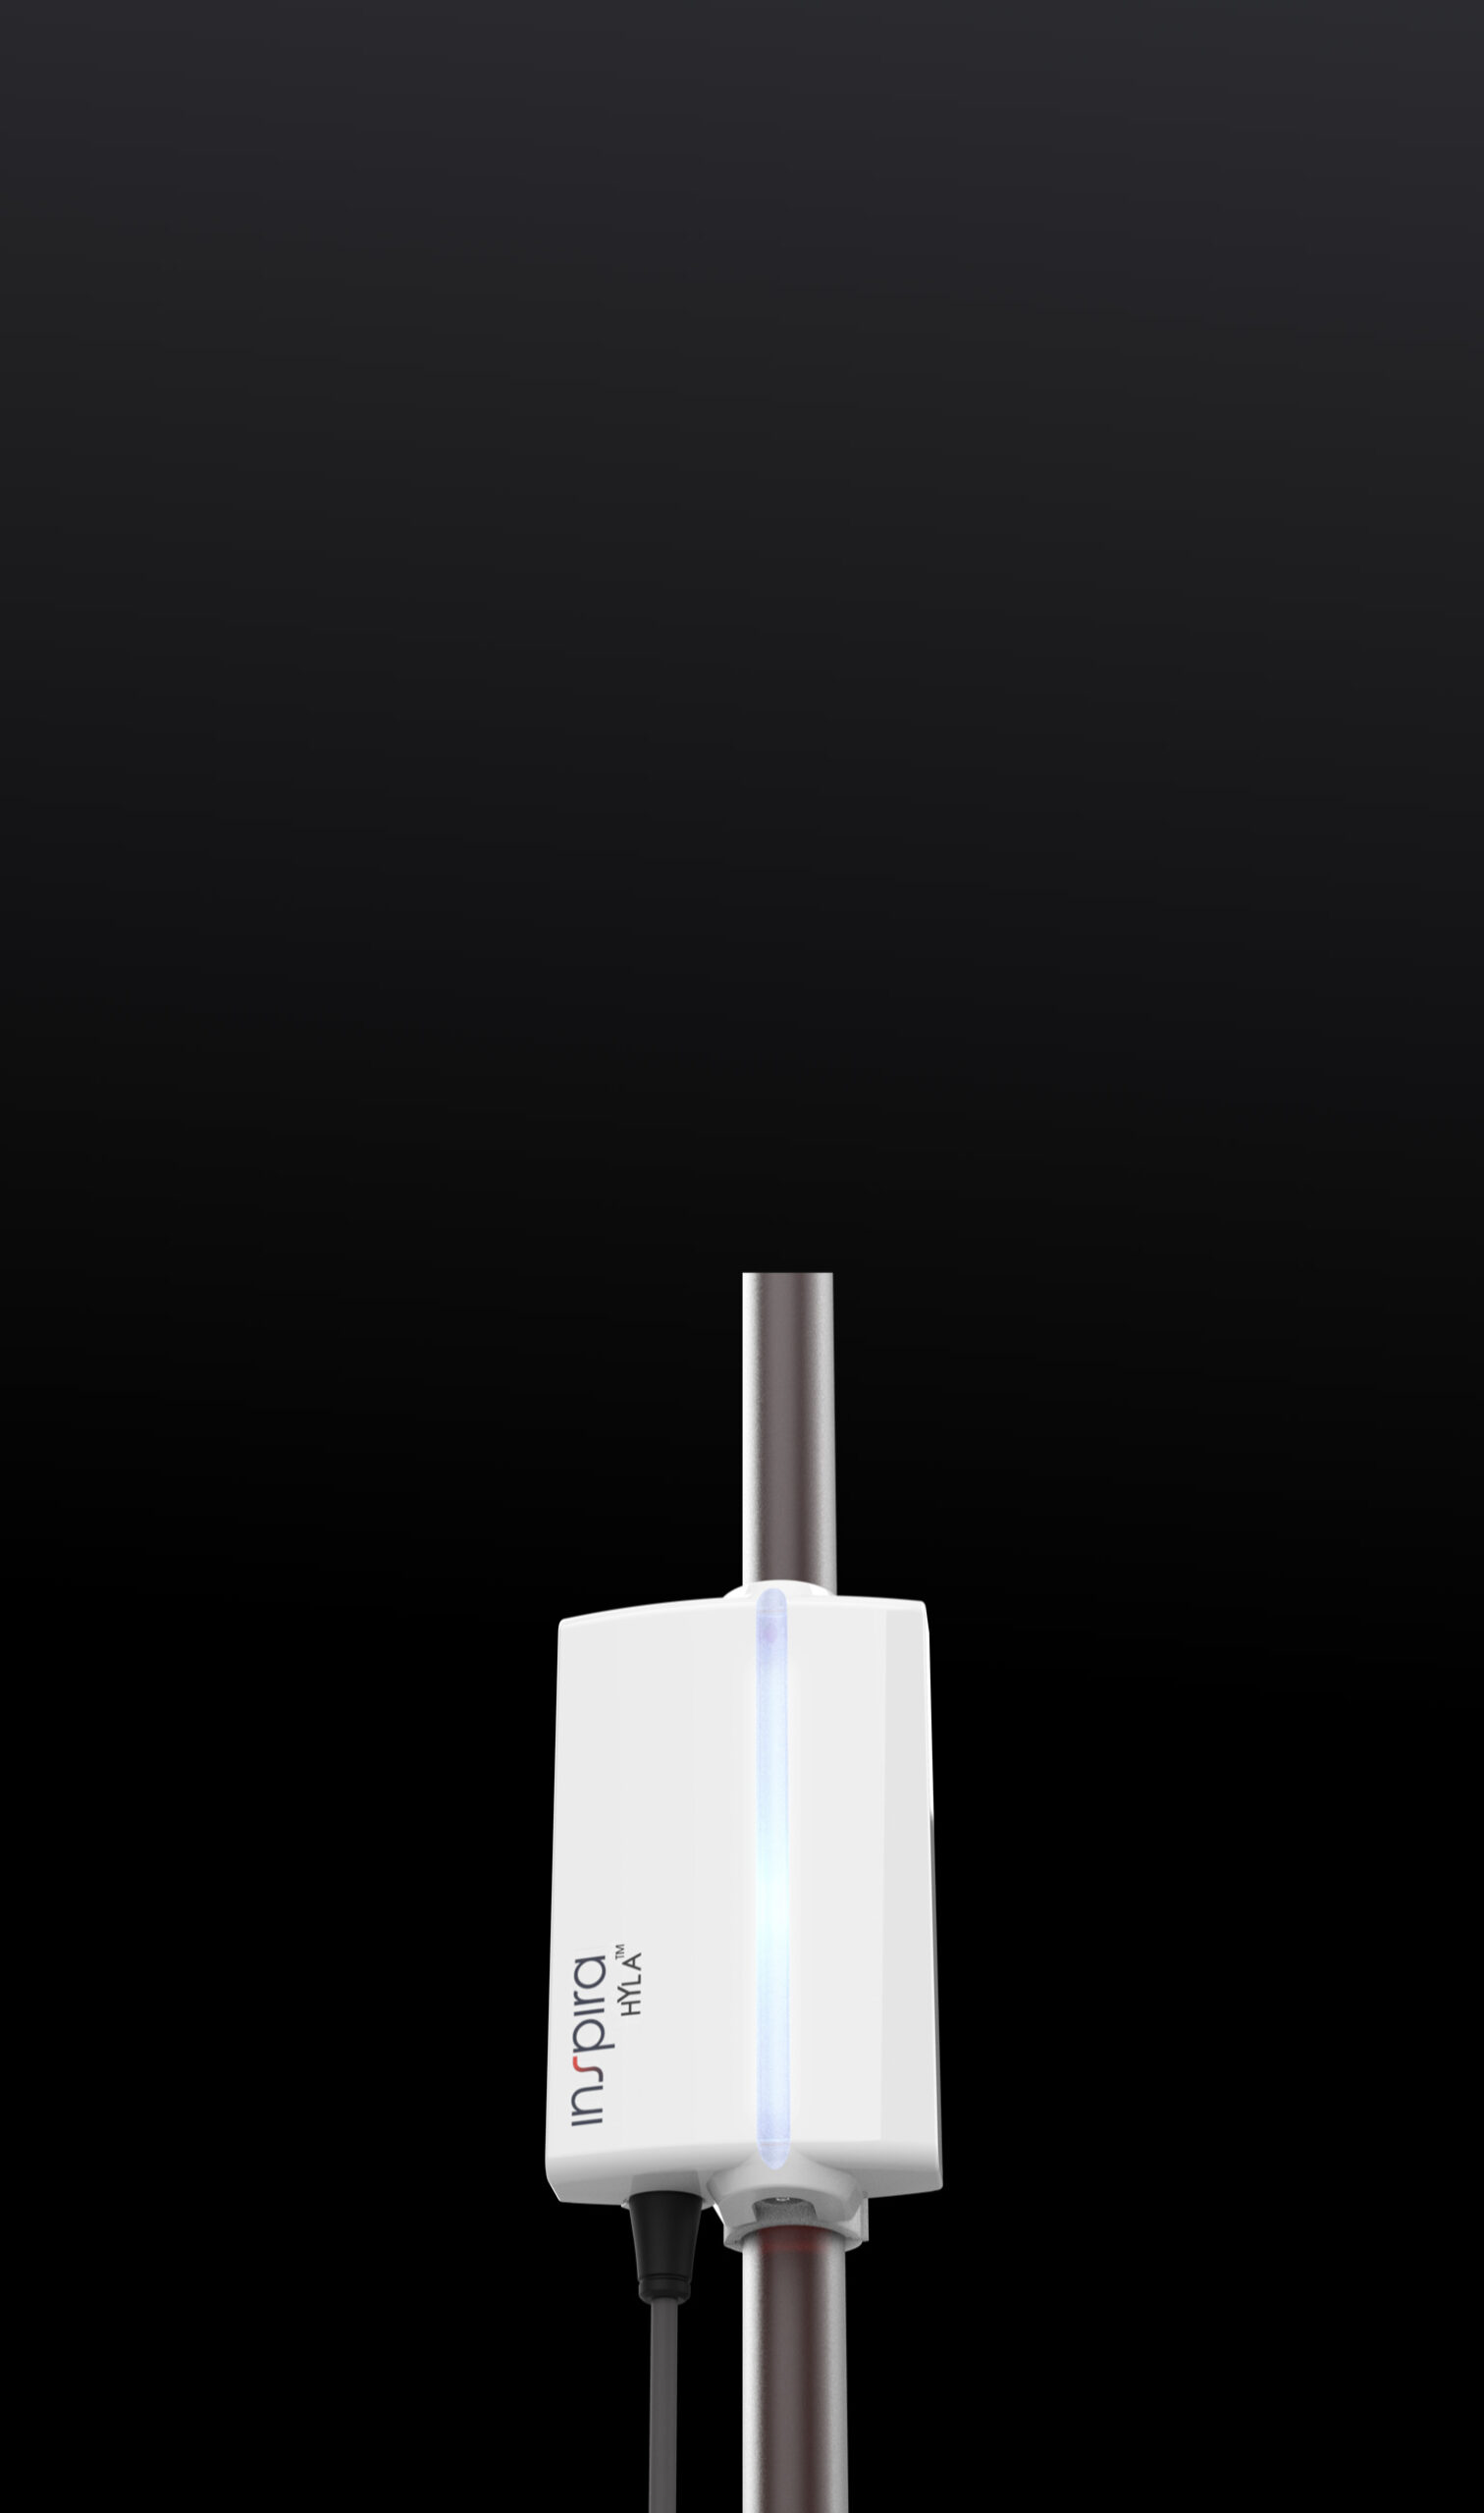

HYLA™ Clip-On Blood Lab

Without the need to take intermittent blood samples, the HYLA™ Optic Blood Lab is designed to test, monitor and alert of sudden changes in key blood parameters.

The HYLA™ Blood Sensor is designed to perform real-time analyzing of blood gases, for patients undergoing medical procedures or requiring more frequent patient monitoring.

The HYLA™ Blood Sensor is designed to perform real-time analyzing of blood gases, for patients undergoing medical procedures or requiring more frequent patient monitoring.

In Clinical Evaluation. Planned FDA Submission 2026